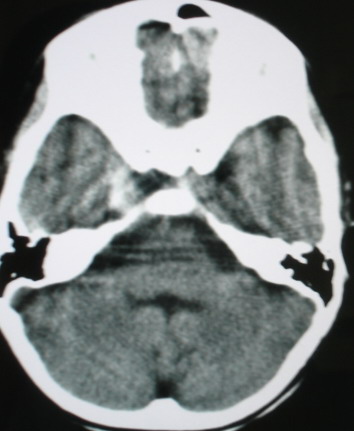

m/8y/,右侧眼睑下垂数日,发育良好,无外伤史,无头痛、恶心、呕吐,学习成绩良好。

ct意见:1、颅内血管畸形。2、右侧海绵窦血管瘤(颈内动脉海绵窦段动脉瘤)。3、脑萎缩。4、建议mr或dsa.

海绵窦瘘.注意眶内静脉有扩张.

右侧海绵窦血管瘤伴右侧海绵窦漏形成(由于右眼上静脉较左侧增粗。故考虑)。

支持 右侧颈内动脉海绵窦瘘.注意眶内静脉有扩张.